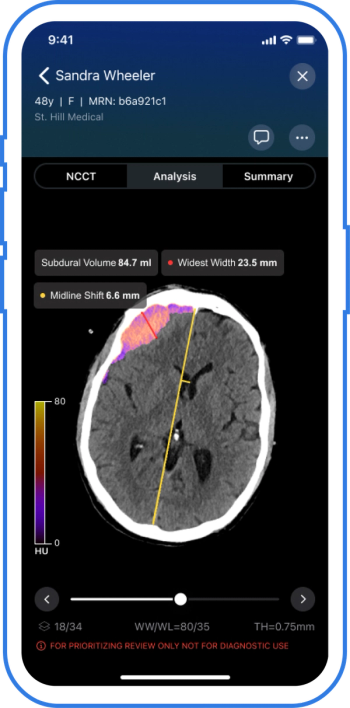

The AI-powered Viz Subdural Plus reportedly provides automated measurements and labeling of subdural collections, including subdural hemorrhages (SDHs), based on non-contrast CT scans.